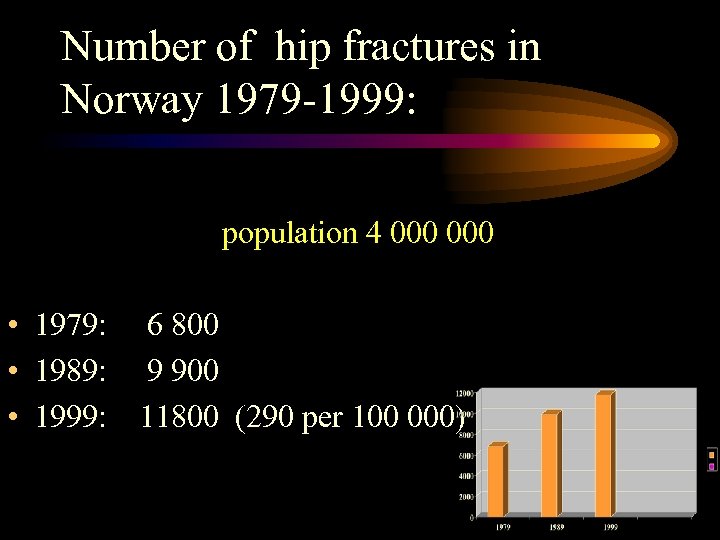

Number of hip fractures in Norway 1979 -1999: population 4 000 • 1979: 6 800 • 1989: 9 900 • 1999: 11800 (290 per 100 000)

Number of hip fractures in Norway 1979 -1999: population 4 000 • 1979: 6 800 • 1989: 9 900 • 1999: 11800 (290 per 100 000)